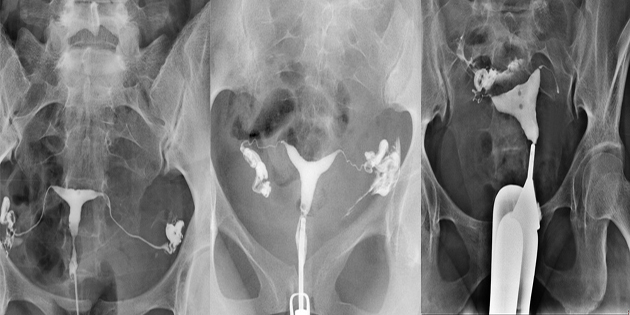

Rahim filmi, tıbbi ismiyle histerosalpingografi (HSG), rahim içi boşluğun ve fallop tüplerinin değerlendirilmesini sağlayan özel bir röntgen işlemidir. Bu yöntemde rahim ağzından içeriye kontrast madde verilir ve bu sıvının rahim ve tüplerden geçişi röntgen altında izlenir. İşlem genellikle adet bitiminden sonra, yumurtlama dönemi başlamadan önce uygulanır.

Kadınların özellikle bebek sahibi olamama şikayetiyle başvurduğu ilk testlerden biridir rahim filmi. HSG sayesinde rahimde doğuştan gelen şekil bozuklukları, yapışıklıklar, miyomlar, polipler ya da tüplerin tıkalı olup olmadığı tespit edilebilir.

Bu işlem sayesinde tüplerin açıklığı net olarak görülebilir. Fallop tüplerinde tıkanıklık varsa, doğal yollarla gebelik oluşması mümkün olmayabilir. Böyle bir durumda tüp bebek gibi yardımcı üreme tekniklerine başvurulması gerekebilir.

Kadınlarda kısırlık nedenlerinin büyük bölümü ya tüplerdeki tıkanıklıklardan ya da rahim içi anormalliklerden kaynaklanır. HSG, bu iki temel alanı doğrudan görüntüleyerek en etkili tanı yöntemlerinden biri haline gelir. Ayrıca bazı durumlarda HSG sırasında verilen kontrast madde, tüplerdeki hafif yapışıklıkları açarak gebelik şansını artırabilir.